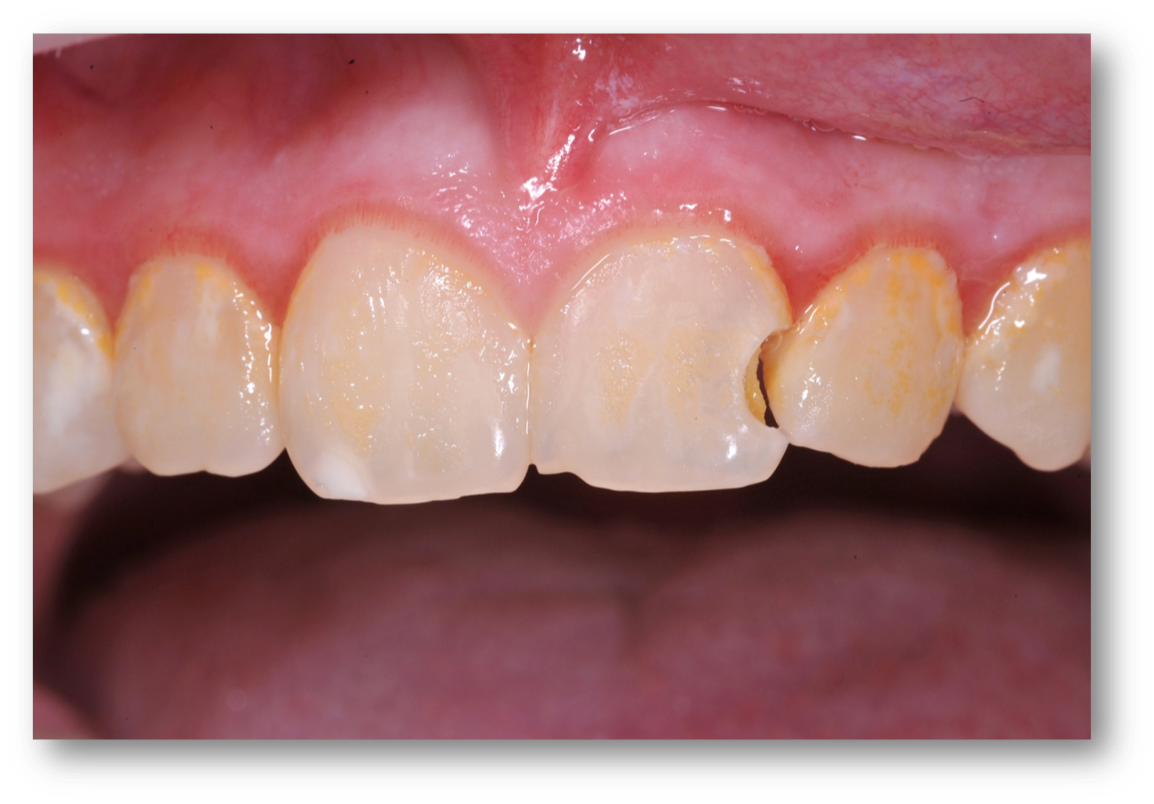

Example 2: Red Gingiva

Red gingiva, as seen in Figure 3, may be caused by a variety of factors, including a lack of brushing, allergies, or drug abuse. Before making a treatment plan, it is important to talk with the patient to try to understand the cause of red gingiva, worn dentition, or erosion.

Fig 3. Red gingiva may be caused by a variety of factors.

Figure 3